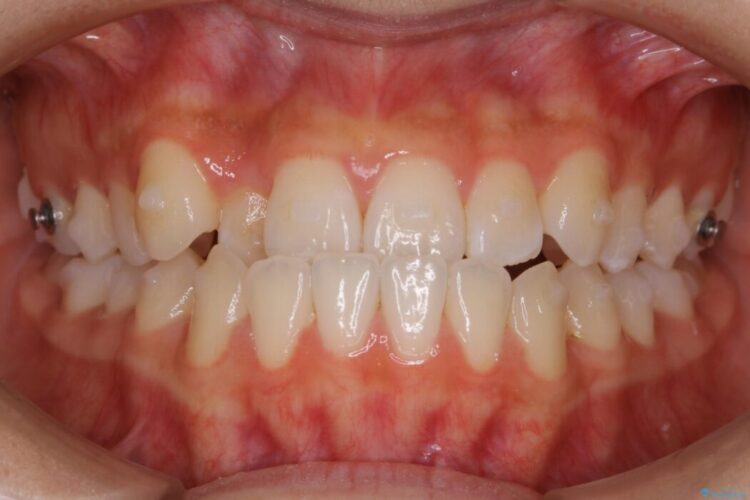

下の歯が上の歯より前に出ている受け口と前歯のガタガタ(叢生)について治療したいとのことで来院されました。

正常な噛み合わせ位置へと改善したことにより奥歯で噛みしめることができ、加えて見た目も受け口から変わって大変ご満足いただけました。

正常な噛み合わせの場合は、上顎の前歯が下顎前歯より前方にあり、覆いかぶさるような状態となります。

反対咬合(受け口)の場合は、その名の通り反対に下顎の前歯が上顎の前歯より前方へ出てきている状態です。